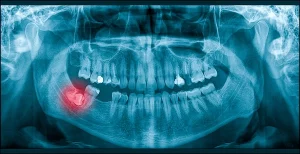

Un centre spécialisé comme celui de Chêne-Bourg prend en charge l’ensemble du parcours. L’évaluation initiale comprend photographies, empreintes numériques et radiographies détaillées. Ces données servent à produire une simulation virtuelle du mouvement des dents, motivant fortement les patients à suivre les consignes.